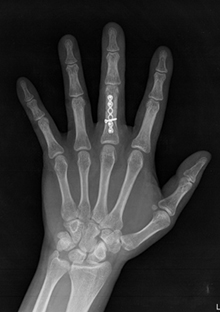

손가락 골절

손가락을 포함한 상지의 골절은 특히 조기 관절운동이 중요합니다.

손가락 골절은 흔히 사용되는 깁스를 포함한 장기간의

고정이나 엉성한 핀고정으로 손가락의 강직을 초래하여

최악의 결과를 낳습니다.

따라서 손가락 골절은 견고하고 정확하게 고정하여

조기에 운동능력을 회복하는 것이 가장 중요합니다.

수술 전 (타병원수술후 변형과 강직이 남은 상태)

수술 후(재수술후 상태)